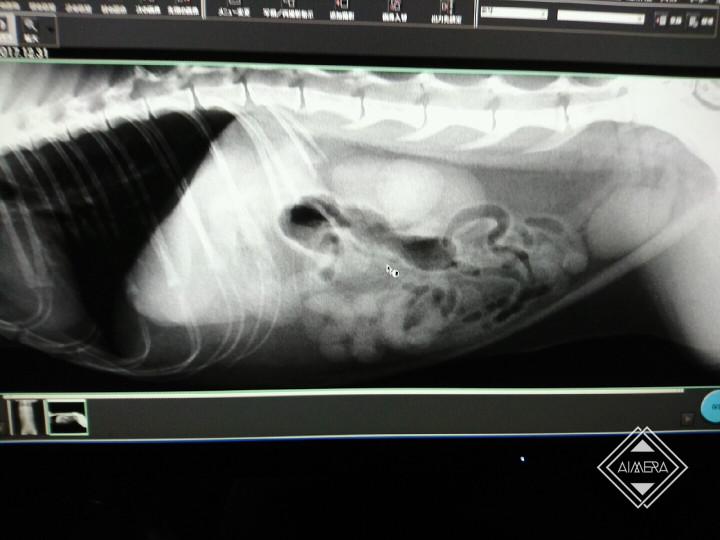

今度は血液検査とレントゲン。誤飲は触診された時にも「ないとは思うけど…」とは言われていたけれど、万が一を考えてお願いした。

けれど結局、どの病状にも当てはまらず、こうなったらレントゲンを見るしかないね、ということになった。

現像が終わったレントゲンを見せてもらい、愕然とした。

確かにアルバはむちっとまるっとずんぐり体型で、胴体が短いなぁ…とは思っていた。なんとなく、だけれど、尻尾のつけ根の骨も、ちょっとだけ変…。

アルバには、本来7本あるはずの腰骨が6本しかなかった。

1本足りないことで、本来の間隔よりも狭く神経が集まるため、高い所から落ちたり、冬場冷え込むと神経痛や、後肢の痺れが出る。